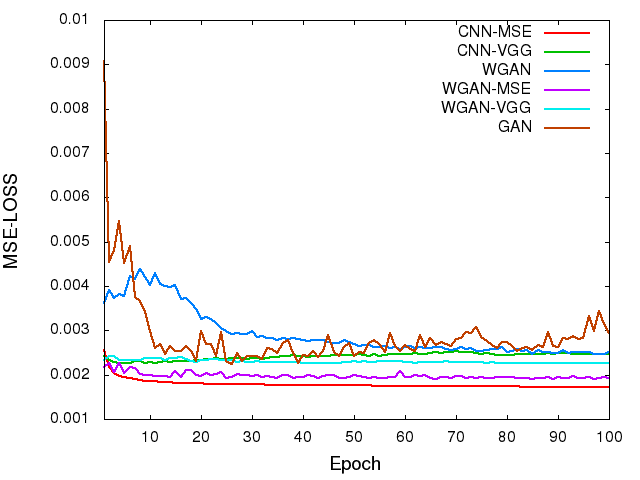

To visualize the convergence of the networks, we calculated the MSE loss and VGG loss over the 5,056 image patches for validation according to Eqs. (4) and (6) after each epoch. Fig. 4 shows the averaged MSE and VGG losses respectively versus the number of epochs for the five networks. Even though these two loss functions were not used at the same time for a given network, we still want to see how their values change during the training. In the two figures, both the MSE and VGG losses decreased initially, which indicates that the two metrics are positively correlated. However, the loss values of the networks in terms of MSE are increasing in the following order, CNN-MSEWGAN-MSEWGAN-VGGCNN-VGG (Fig. 4a), yet the VGG loss are in the opposite order (Fig. 4b). The MSE and VGG losses of GAN network are oscillating in the converging process. WGAN-VGG and CNN-VGG have very close VGG loss values, while their MSE losses are quite different. On the other hand, WGAN perturbed the convergence as measured by MSE but smoothly converged in terms of VGG loss. These observations suggest that the two metrics have different focuses when being used by the networks. The difference between MSE and VGG losses will be further revealed in the output images of the generators.

In order to show the convergence of WGAN part, we plotted the estimated Wasserstein values defined as in Eq. (3). It can be observed in Fig. 4(c) that increasing the number of epochs did reduce the W-distance, although the decay rate becomes smaller. For the WGAN-VGG curve, the introduction of VGG loss has helped to improve the perception/visibility at a cost of a compromised loss measure. For the WGAN and WGAN-MSE curves, we would like to note that what we computed is a surrogate for the W-distance which has not been normalized by the total number of pixels, and if we had done such a normalization the curves would have gone down closely to zero after 100 epochs.